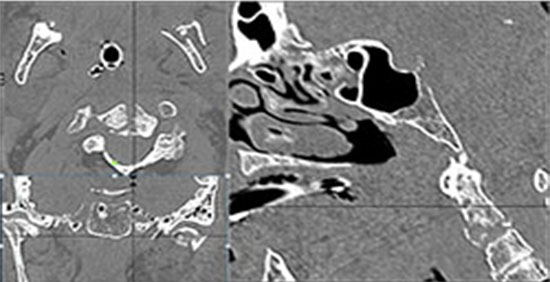

Right Temporal Bone

The external auditory canal shows abnormal soft tissue thickening.

The ossicles, in particular the incus long process, the incudostapedial joint and stapes are fractured or dislocated.

The facial canal including the labyrinthine, tympanic and descending portions and nerve are fractured.

The inner ear including the lateral semicircular canals, vestibule and/or cochlea is fractured or otherwise abnormal.

Left Temporal Bone